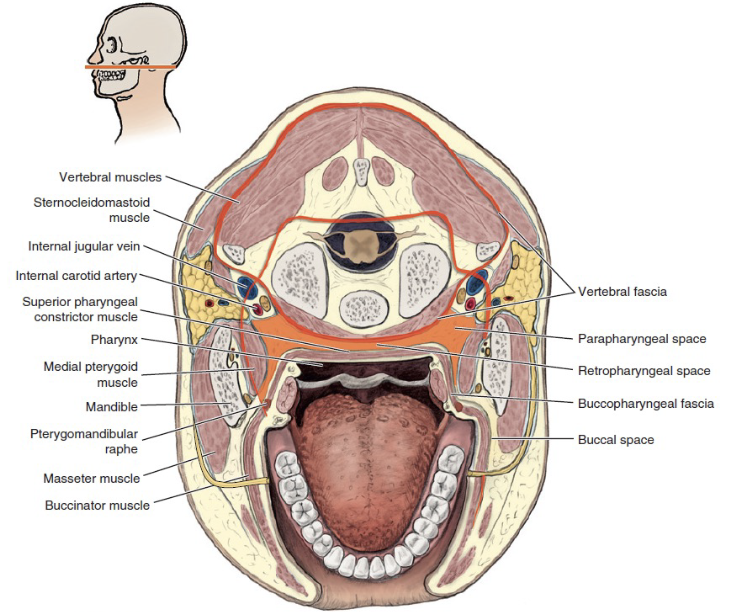

Buccal space

- Buccal fat pad

- Parotid duct

- Facial a.

Parotid space

- Parotid g.

- Facial n.

- ECA

- Retromandibular v.

Masticator space

Temporal space

Temporalis m.分隔

- Superficial temporal space

- Deep temporal space

Infratemporal space

Zygomatic arch 以下

- 外側

- Temporalis

- 內側

- Pterygoid plate

- Maxillary a.

Pterygomandibular space

Med. pterygoid m.外

- Inf. alveolar a./ v./ n.

- Lingual n.

Submassetric space

Parapharyngeal space

Retropharyngeal space

- Dangerous space

- Sup. pharyngeal constrictor m.後